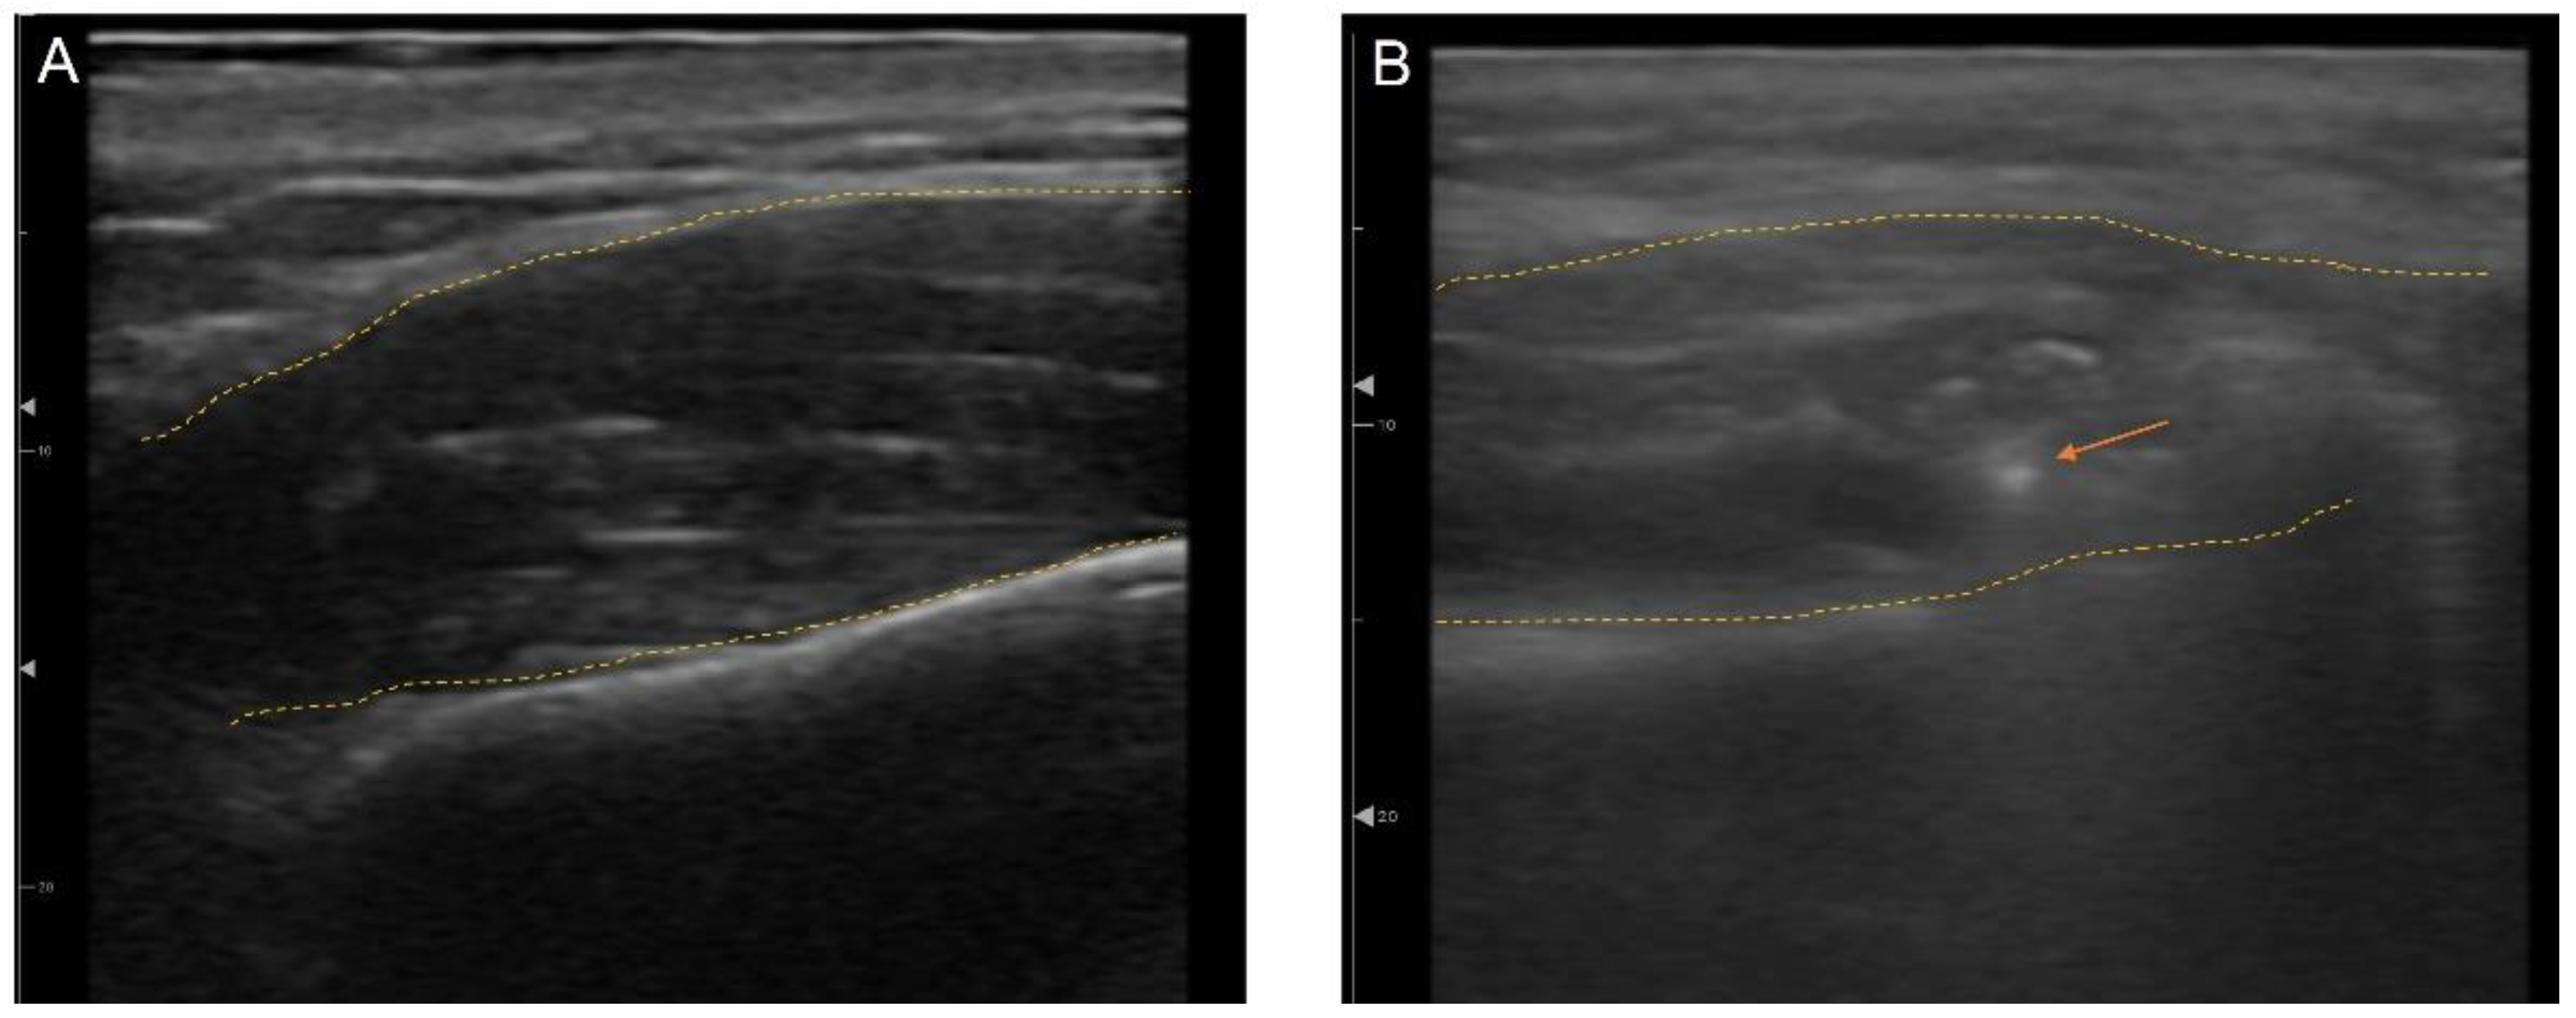

3.5. Ultrasonography (US)-Guided Botulinum Toxin Techniques